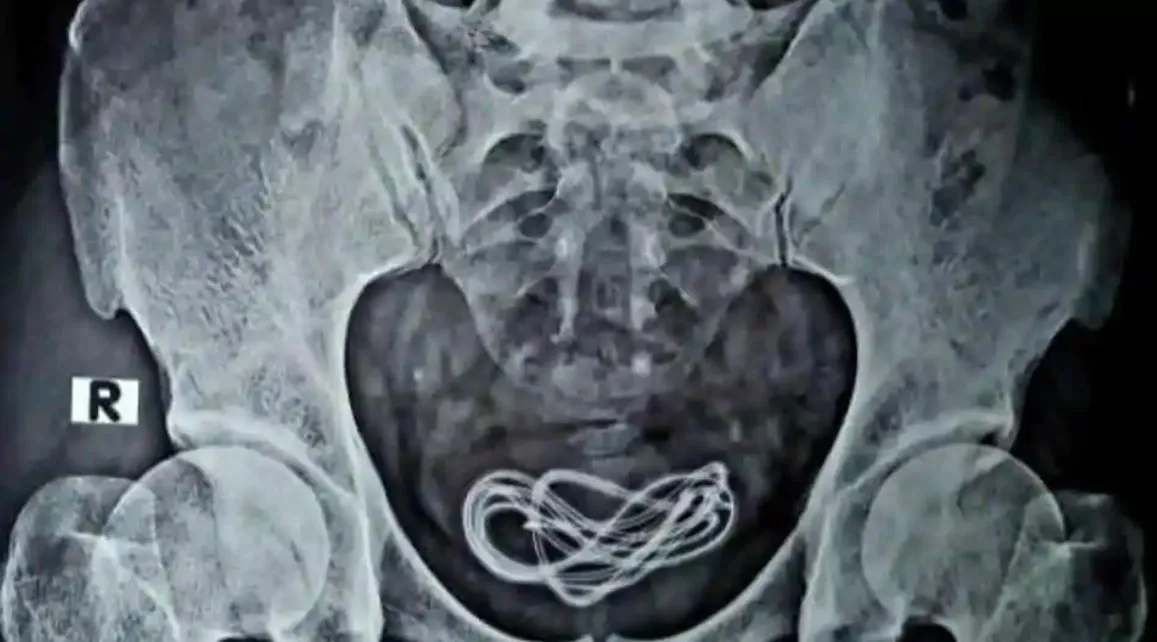

Endoszkópos beavatkozásra került sor, de a gyomor-bélrendszeri traktusban nem találtak semmit. Aztán egy röntgen kimutatta: az idegen test jóval lejjebb található. A húgyhólyagban.

A beteg ekkor bevallotta, hogy húgycsövén át juttatta be a töltőkábelt a szervezetébe. A vezetéket (mármint a töltőét) eltávolították, a férfi a hírek szerint szépen gyógyul.